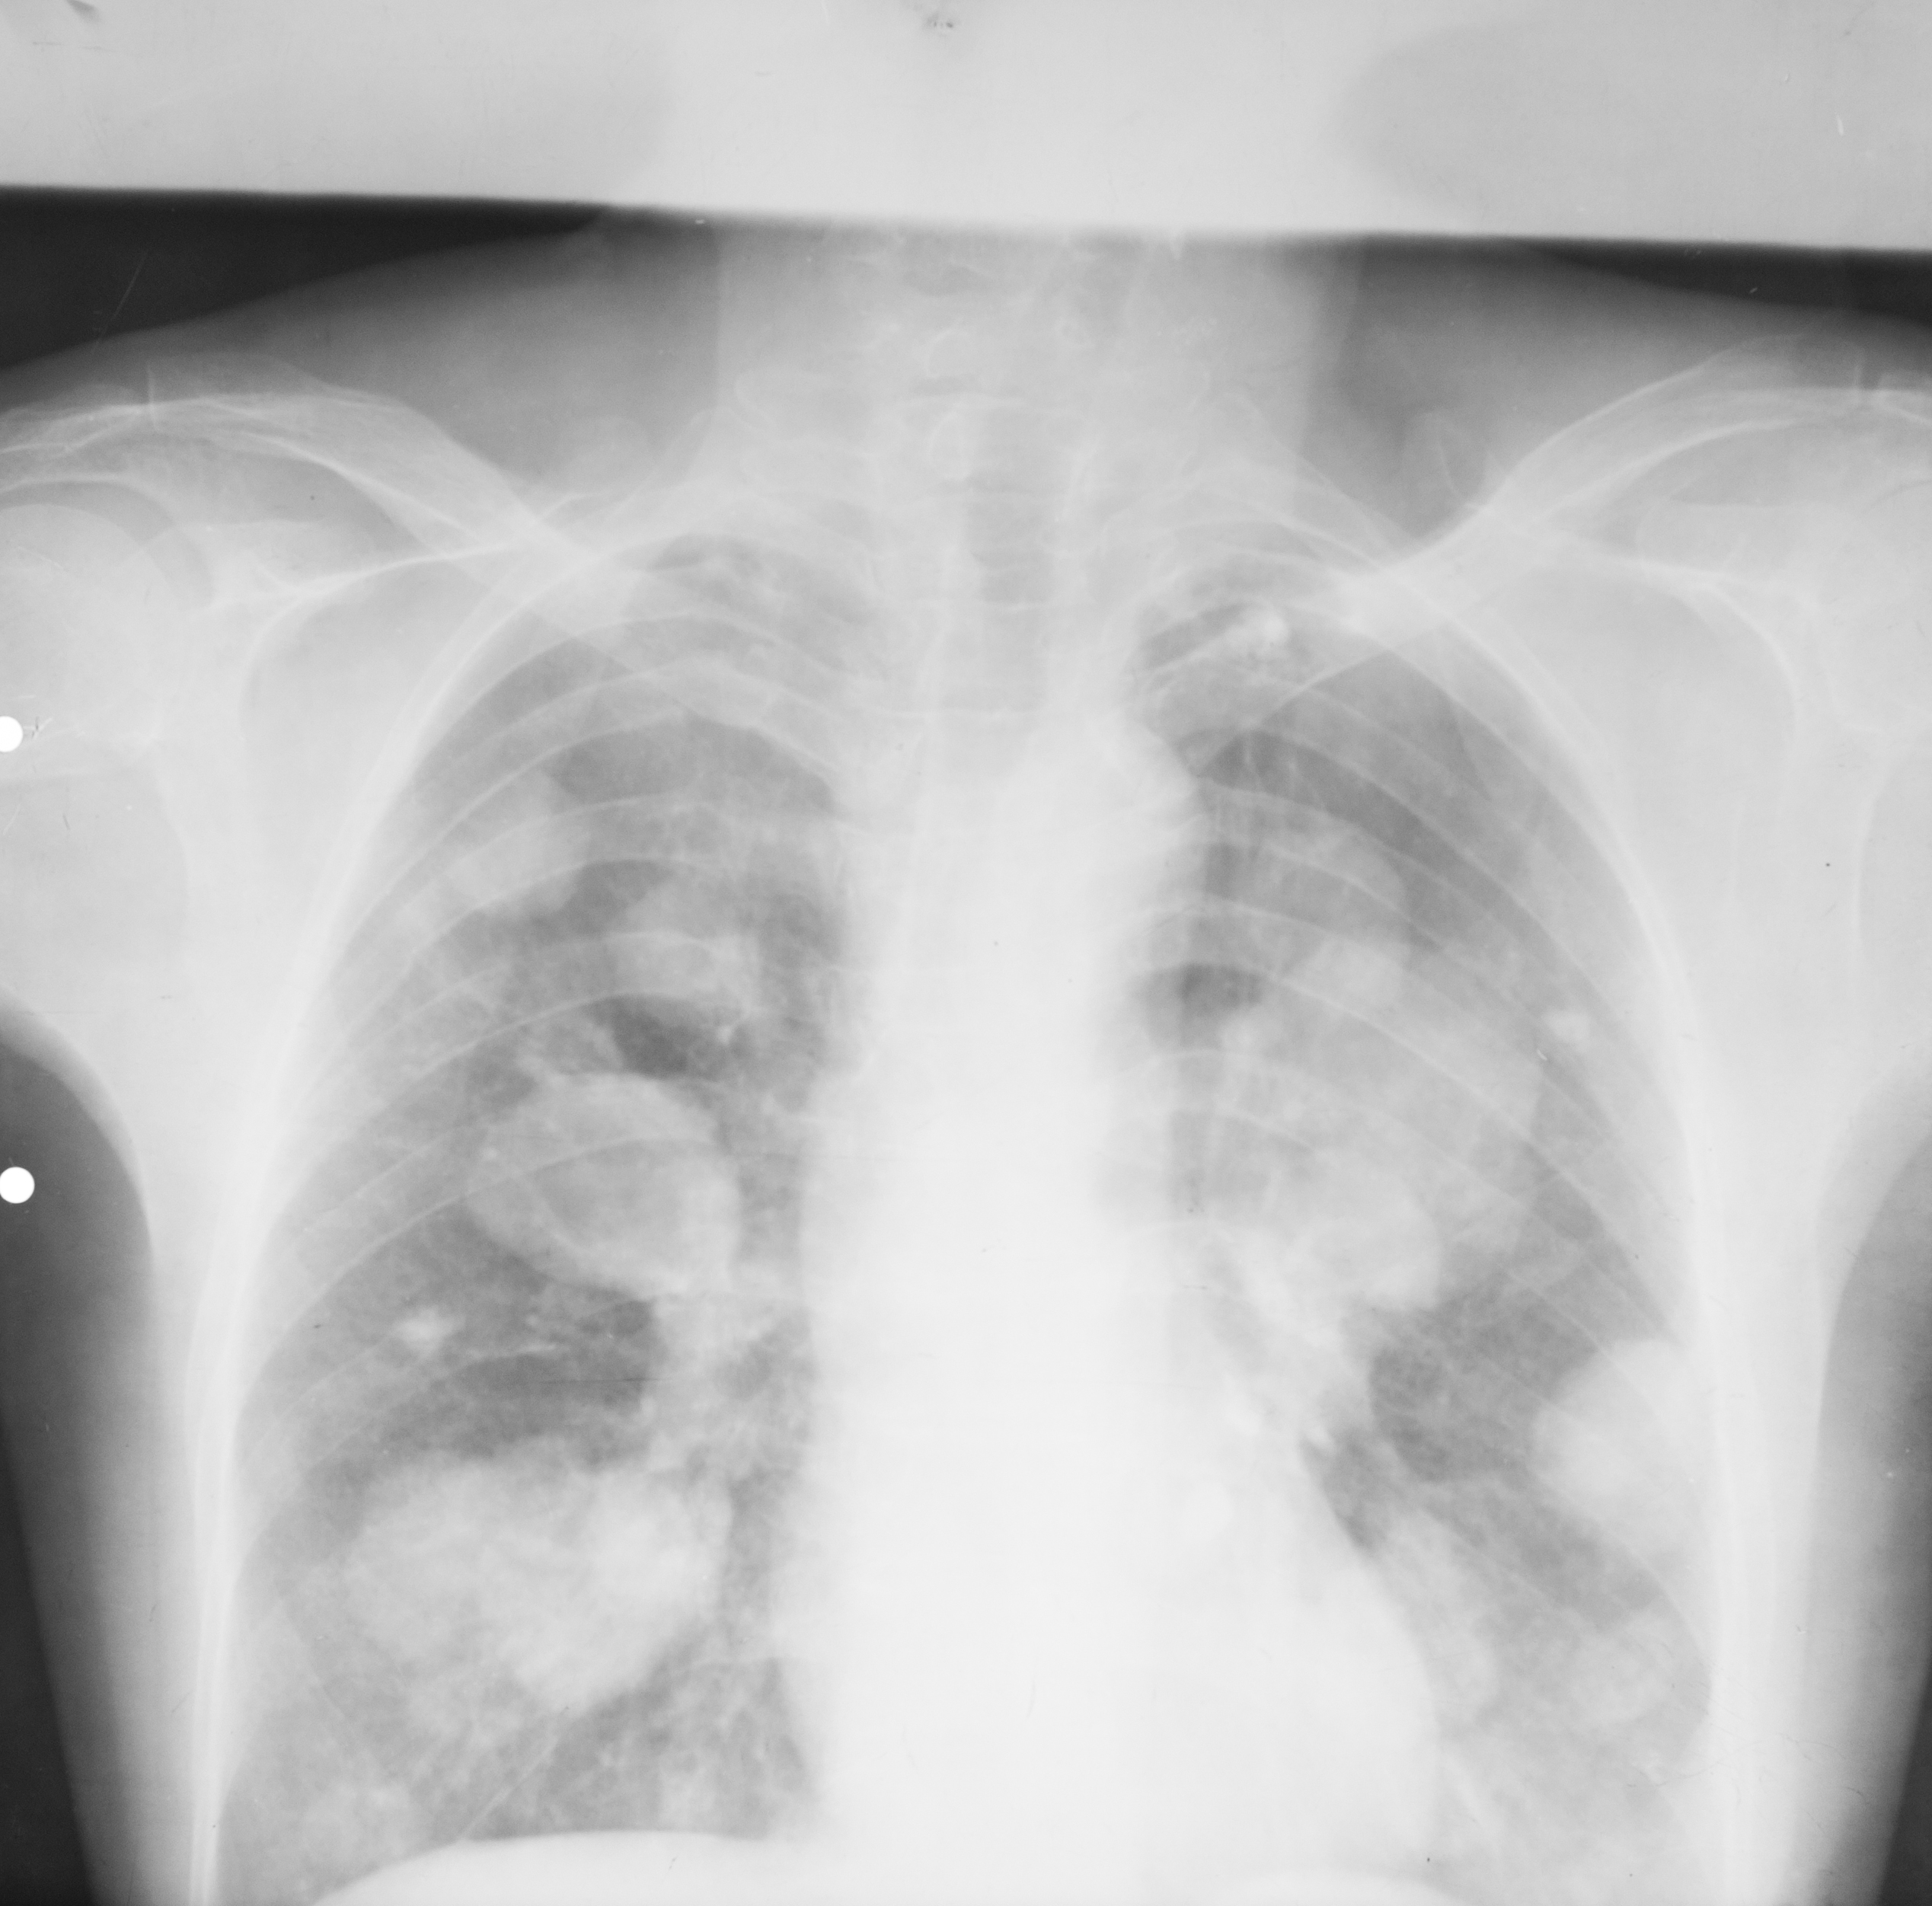

Rx toraco-mediastino-pleuro-pulmonar – opacități multiple de dimensiuni variabile situate mai degraba la bazele pulmonare,de intensitate medie-slaba,unele mai intense,altele mai putin intense,contururile plu ? – sunt procese de condensare avand in vedere aspectul acesta plu si undeva situat bazal – probabil bronho-pneumonie

METASTAZE PULMONARE

Opacități bine,net liniar delimitate,având aproximativ aceeași intensitate,prezente în ambele câmpuri pulmonare(opacități=procese de condensare).